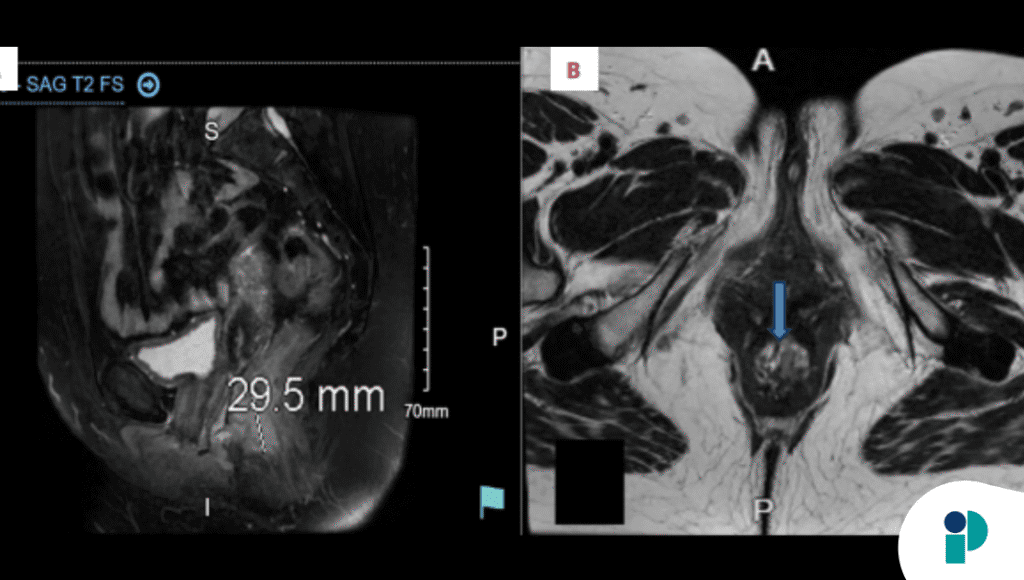

Una resonancia magnética corroboró que el tumor estaba limitado al recto, con invasión de la muscular propia pero sin afectación más allá de la serosa ni metástasis. La mujer fue remitida al servicio de oncología para tratamiento definitivo.